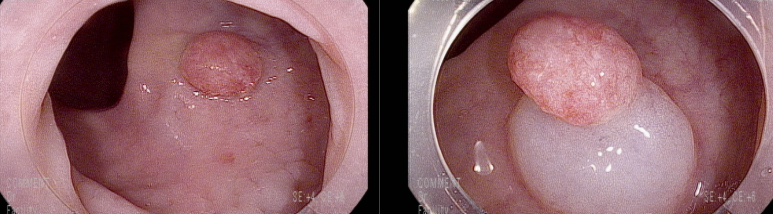

휴지에 묻는 정도의 항문 출혈로 내원, 직장의 retention polyp(juvenile polyp, 연소성 용종)

30대 남자

휴지에 묻는 정도의 항문출혈로 내원

대장내시경 8 mm의 경을 가지는 용종이 직장하부에서 관찰되어 용종절제술로 제거함, 표면은 발적이 있으며 지저분한 염증성 양상임

Consistent with Retention polyp

연소성 용종

무증상 소아의 약 1%에서 발견되는 흔하지 않은 용종으로 주로 10세 이하의 소아에서 발생한다고 한다. 연소성 용종의 빈도는 전체 대장 용종의 4.4%에 해당하고, 연소성 용종의 15%는 성인에서도 발견된다. 주로 남자에 많고 직장 출혈이 주증상이다. 대부분이 하부대장에 호발하고 연소성 용종의 90% 이상이 항문연으로부터 20 cm 이내에 있다고 보고되었다.